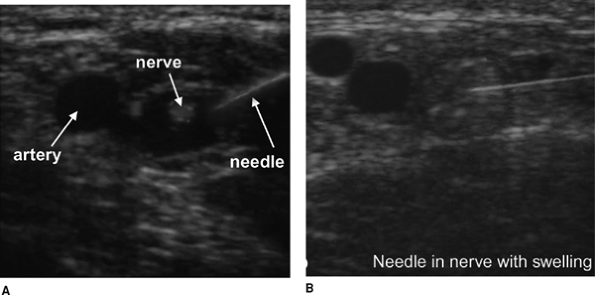

usually a potential space between the fascia and the epineurium. When a

needle punctures the fascia, local anesthetic can usually be deposited

between the fascia and nerve. This creates a black (hypoechoic) ring

around the nerve. In some cases the fascia adheres to the epineurium or

is missing. In that case, the needle may puncture the nerve and the

nerve will swell as the local anesthetic is injected (Fig. 32-7A, B).

Figure 32-7.

When a needle punctures the fascia, local anesthetic can usually be

deposited between the fascia and nerve. This creates a black

(hypoechoic) ring around the nerve. -